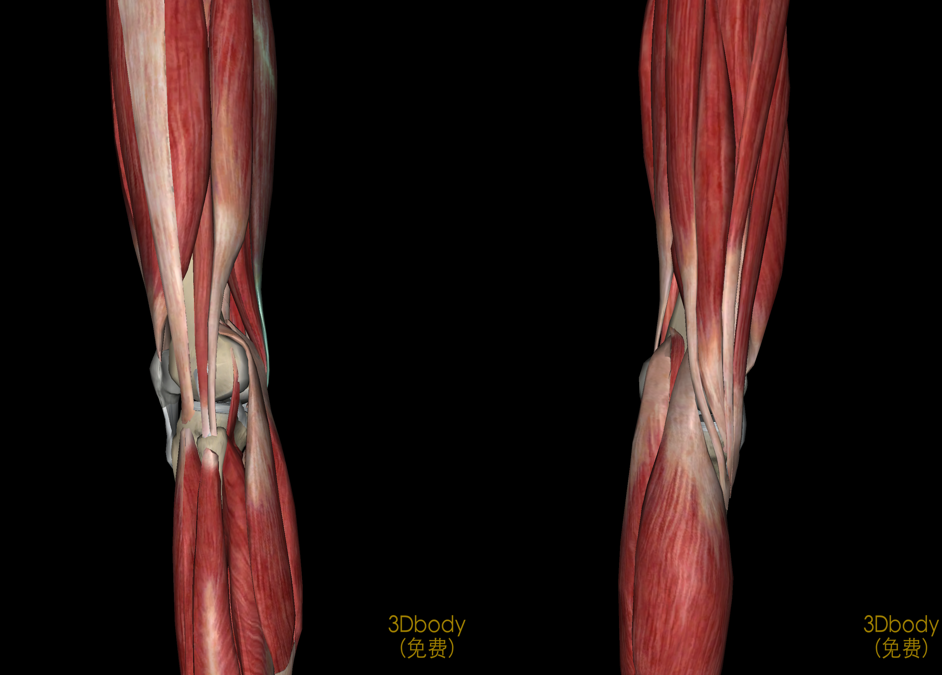

膝关节解剖

病因和发病机制关节的基本结构:关节面、关节软骨、关节腔、关节囊关节软骨:厚度约为2-7mm软骨表面光滑,摩擦系数很小,故有利于关节活动。